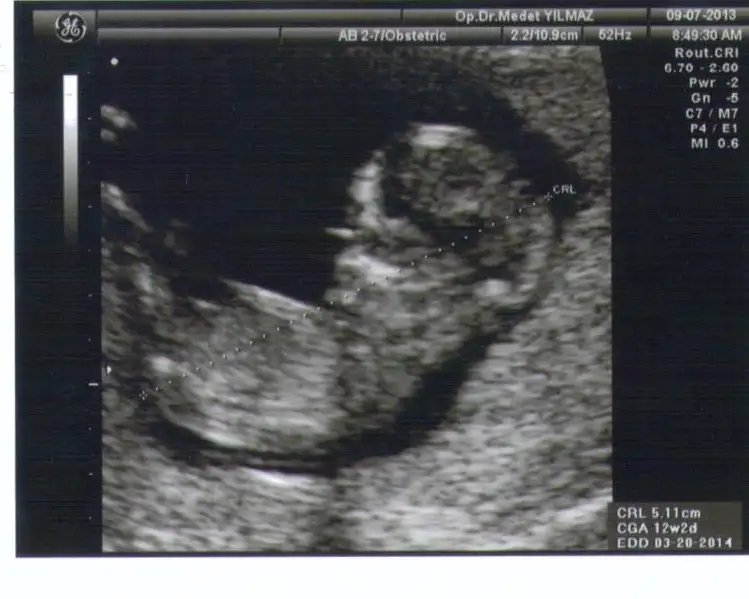

cnm benm resmimede bi yorum yapar mısın shzofren arkadaşım göremedi arkasını dönmüş dedi ama doktor ultrasonu bana çevirdiğinde nubunu gördüm ben açık seçik yukarı bakıyordu bide sen bi bak canm nub görünüyor mu doktor inatla 20 haftadan önce söylemem dedi cinsiyetini:44: $IMG_20130905_120503.webp

cnm benm resmimede bi yorum yapar mısın shzofren arkadaşım göremedi arkasını dönmüş dedi ama doktor ultrasonu bana çevirdiğinde nubunu gördüm ben açık seçik yukarı bakıyordu bide sen bi bak canm nub görünüyor mu doktor inatla 20 haftadan önce söylemem dedi cinsiyetini:44:Eki Görüntüle 797104

kizlar inanin net birsey gorunmuyor uzgunummmm:50: